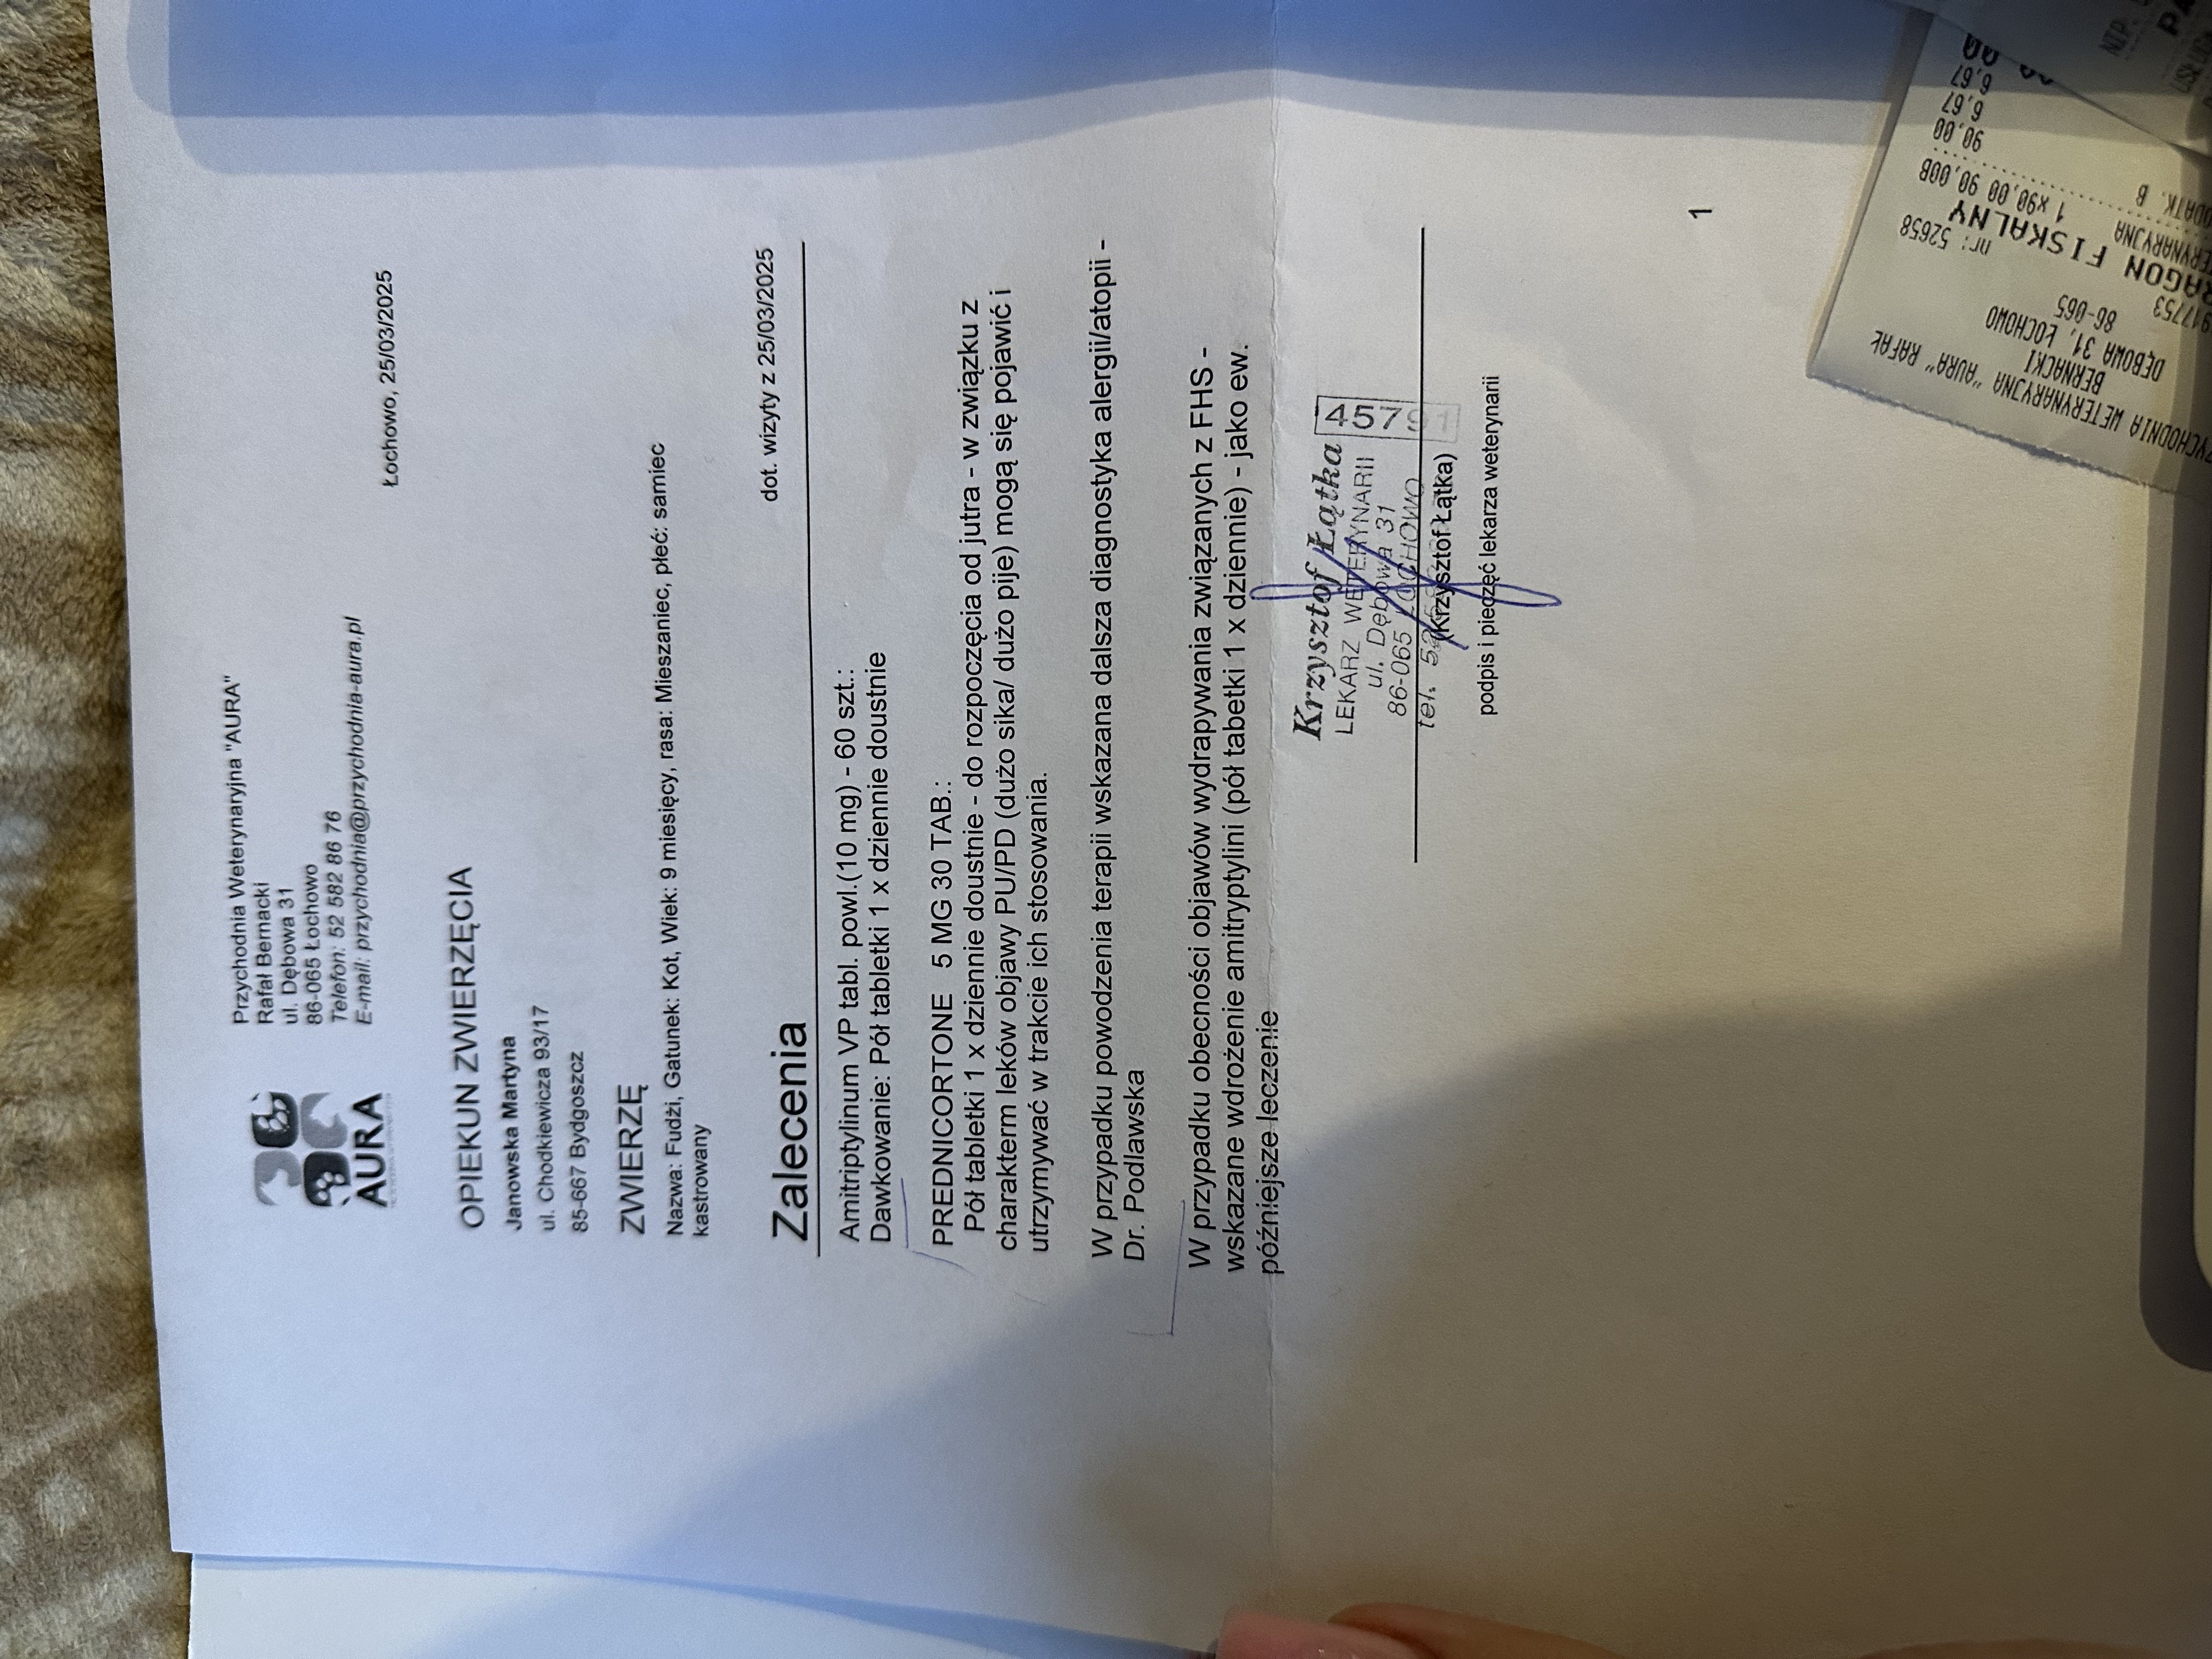

Pojawiło się podejrzenie Feline Hyperesthesia Syndrome (FHS) – zaburzenia neurologicznego, które może powodować nadwrażliwość skóry, niekontrolowane reakcje bólowe oraz zmiany w zachowaniu, a także zostało przeprowadzone badanie kliniczne i nie wykluczono problemów dermatologicznych w związku z agresywnym wydrapywaniem futerka (alergia, pasożyty). Zalecono obserwację i sprawdzenie reakcji na leki sterydowe.

Lekarz wprowadził leczenie objawowe, aby sprawdzić, czy Fudżi dobrze na nie zareaguje: Amitryptylina – lek przeciwdepresyjny i przeciwbólowy, stosowany przy zaburzeniach Pnrednicorton (steryd) – silny lek przeciwzapalny, mający zmniejszyć stan zapalny i świąd.

Fudżi nadal wymaga diagnostyki oraz możliwego rozszerzenia leczenia. Jeśli obecna terapia sterydowa przyniesie poprawę, konieczne będzie wykonanie dalszych badań w kierunku alergii/atopii i nie potwierdzi się występowanie zespołu FHS.